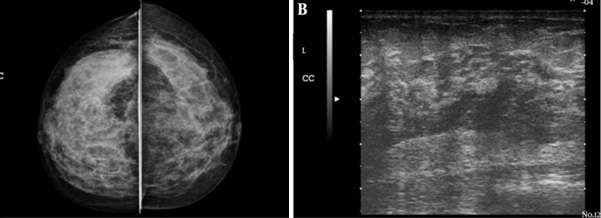

Idiopathic granulomatous mastitis is another uncommon type of non-lactational mastitis that is usually seen a few years after lactation. The etiology and pathophysiology are also unclear but are currently thought to be related to an autoimmune process against specific antigens in extravasated milk. A reaction to breast trauma, subclinical infection (specifically with Corynebacterium species), and hyperprolactinemia have also been implicated in the etiology. It is thought that the resultant destruction of acini and milk ducts causes leakage of milk into breast tissue, triggering a localized inflammatory cellular infiltrate and ultimately a granulomatous response. Granulomatous mastitis usually presents as a unilateral firm breast mass, with or without skin thickening and ulceration, nipple retraction, and adenopathy. Often, patients present with extramammary symptoms including arthralgias and skin changes. Mammographic and sonographic appearance is variable. Mammograms are often normal but can also demonstrate asymmetrically increased density or multiple benign or malignant appearing masses. Ultrasound findings can include a mass-like appearance, tubular or nodular hypoechoic structures, or an ill-defined hypoechoic area. In the workup of this condition, other causes of granulomatous disease should be excluded, including sarcoidosis, granulomatosis with polyangiitis, tuberculosis, and fungal infection. Additionally, given similarity in presentation and imaging appearance, an underlying breast cancer should be excluded, and diagnosis is usually confirmed with biopsy of suspicious lesions. Complications also include abscess and fistula.